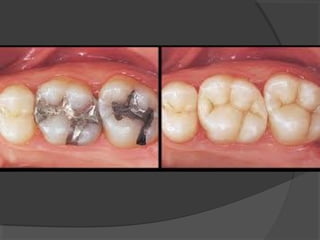

 Amalgam has been an accepted part of dental

therapeutics for more than 150 years and is still used

for more than 75% of direct posterior restorations.

The reasons for its popularity lie in its ease of

manipulation, relatively low cost, and long life.

Some concern has been raised about mercury

toxicity from both a biologic and an environmental

point of view; however, it is believed that dental

amalgam presents an acceptable risk-to-benefit ratio

when properly used.